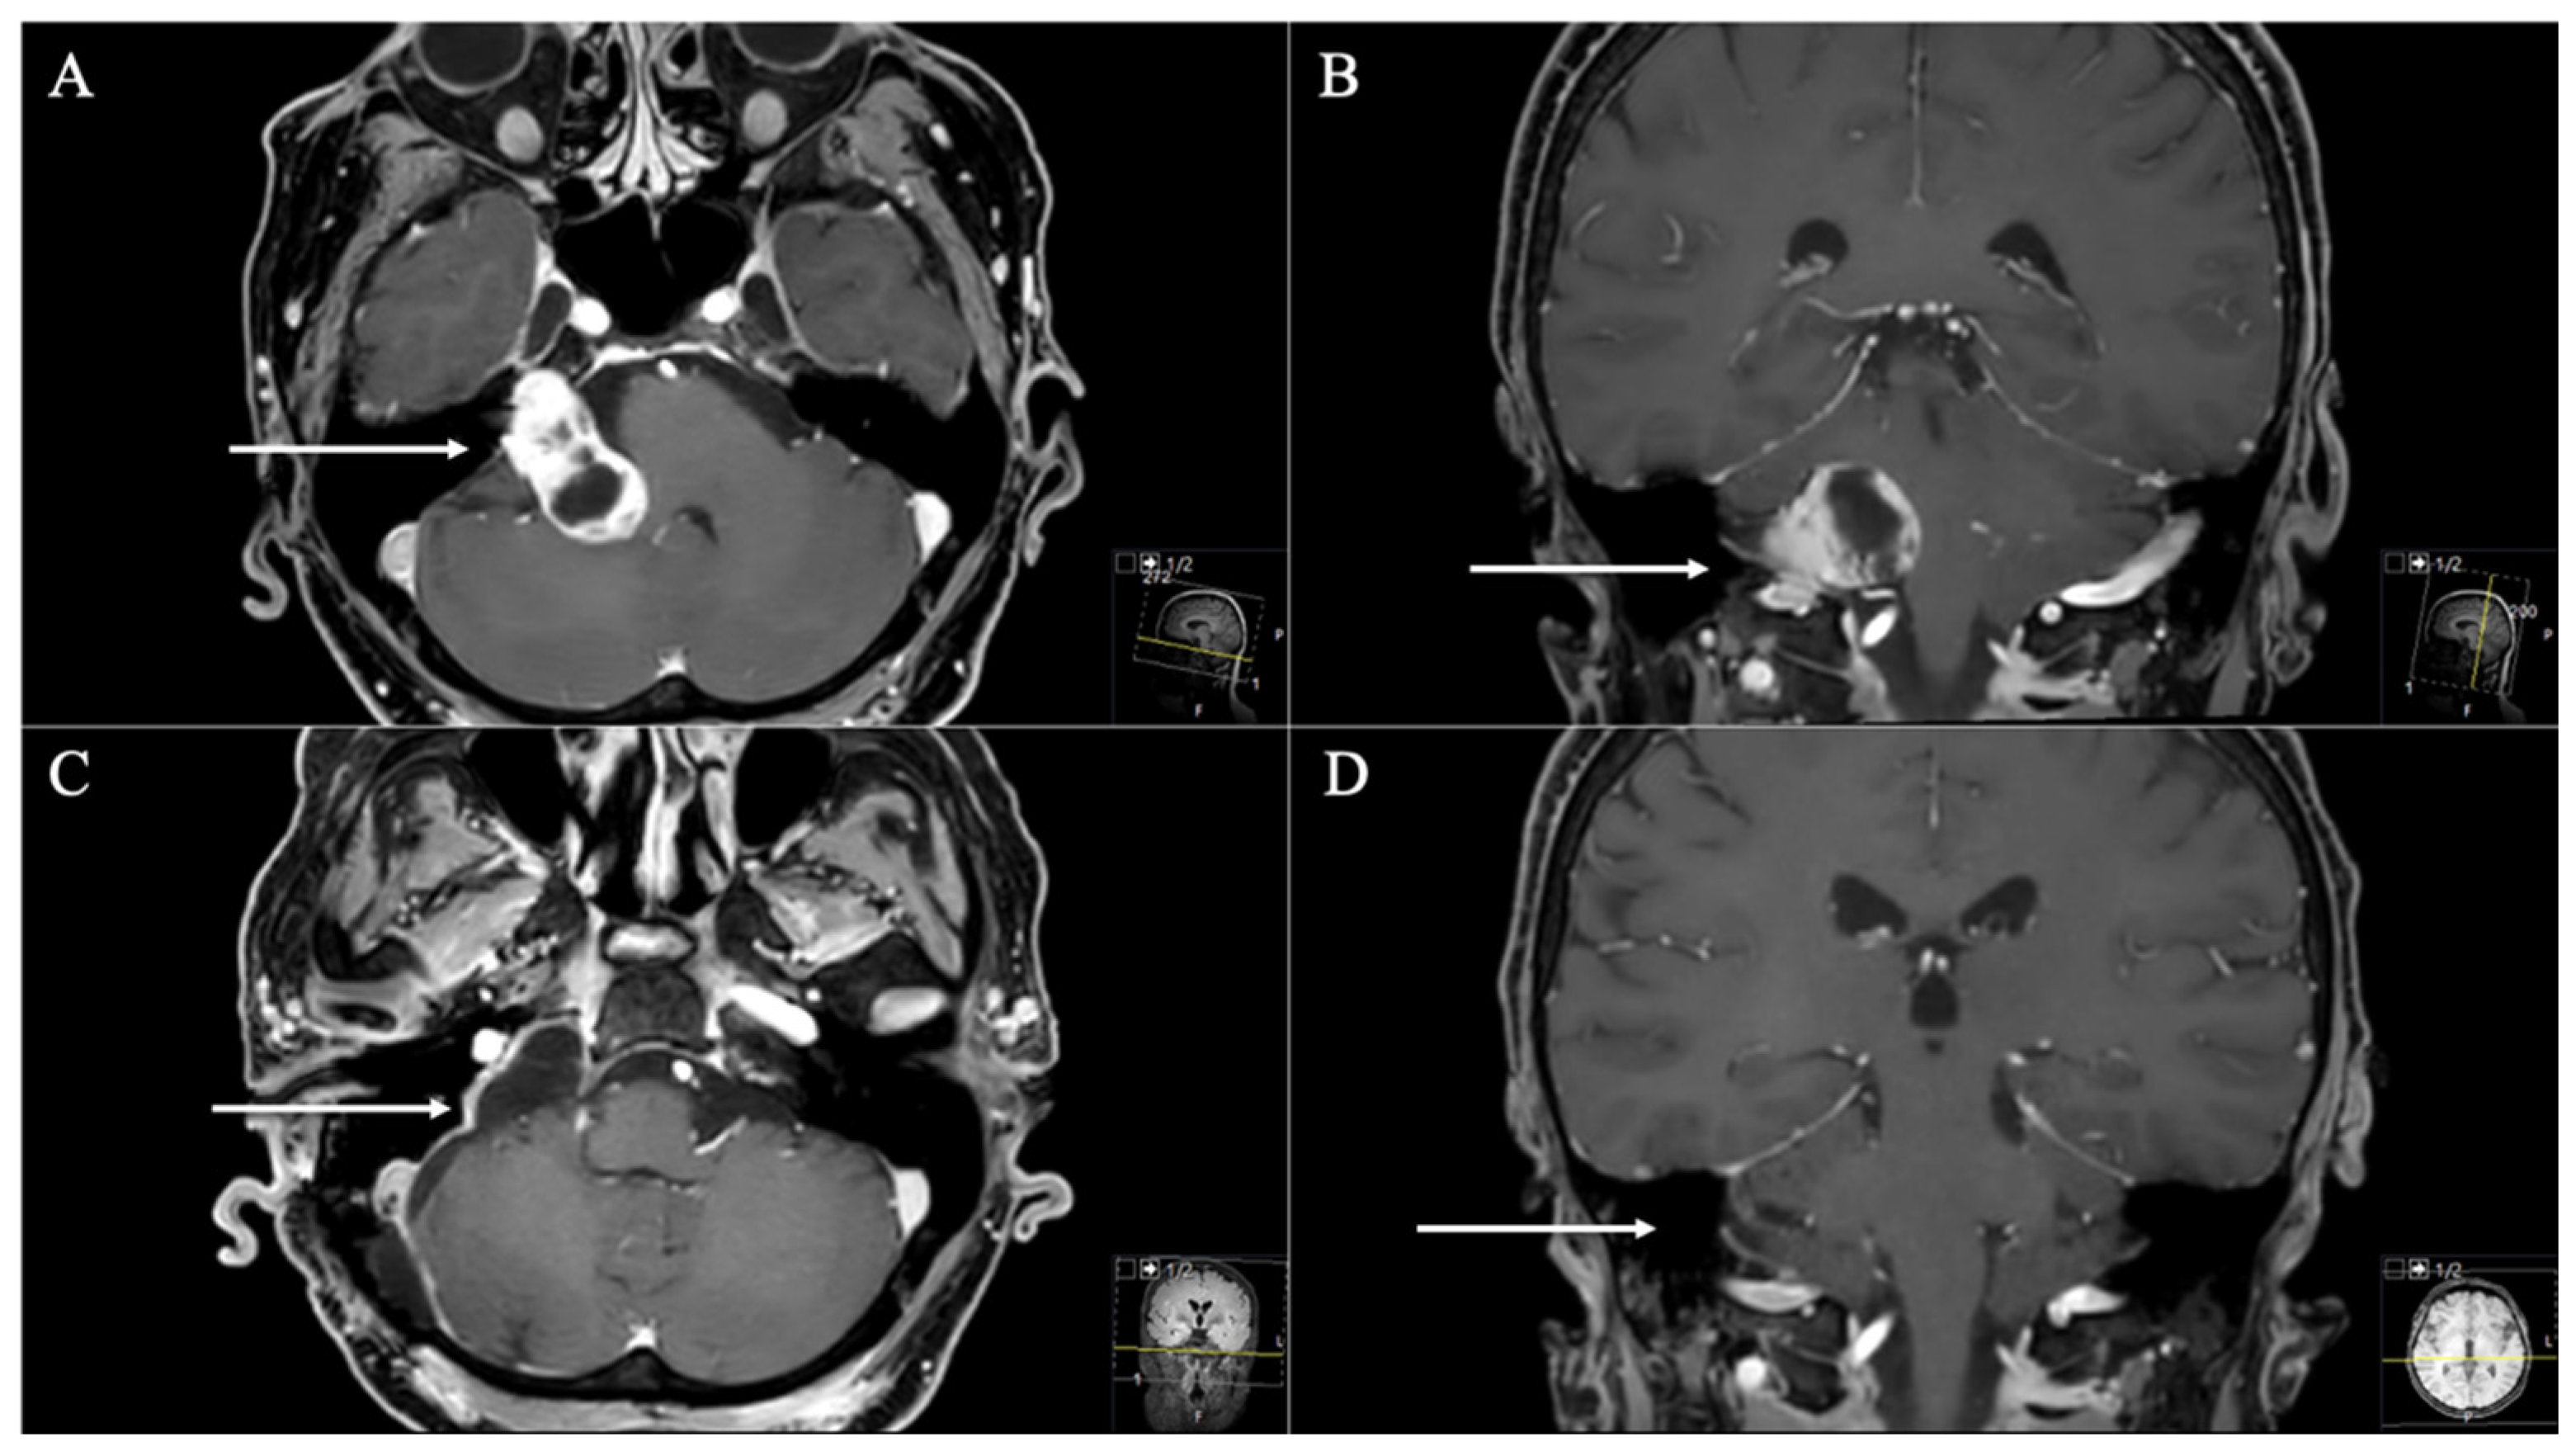

2.3. Surgical Approaches

2.3.1. Retrosigmoid Approach

2.3.2. Extreme Lateral Infrajugular Transcondylar (ELITE) Approach